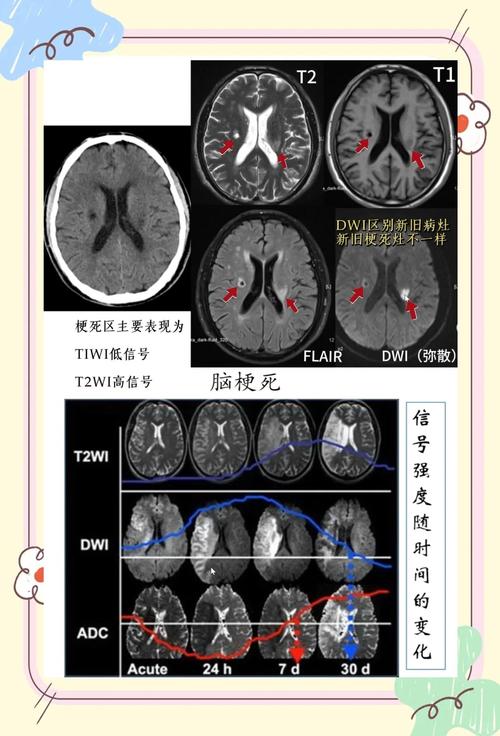

MRI可以提供T1加权像、T2加权像、FLAIR(液体衰减反转恢复)、DWI、PWI(灌注加权成像)等多个序列,通过综合分析这些序列,医生不仅能判断是否存在脑梗,还能评估梗死的范围、时间(是新发还是陈旧)、以及脑组织的血流灌注情况,这对于指导治疗(如是否适合溶栓)至关重要。

- 新旧病灶并存: 患者既有新发的急性脑梗,又有陈旧的小软化灶,如果阅片不仔细,可能会漏掉新病灶或将陈旧灶误认为新病灶。